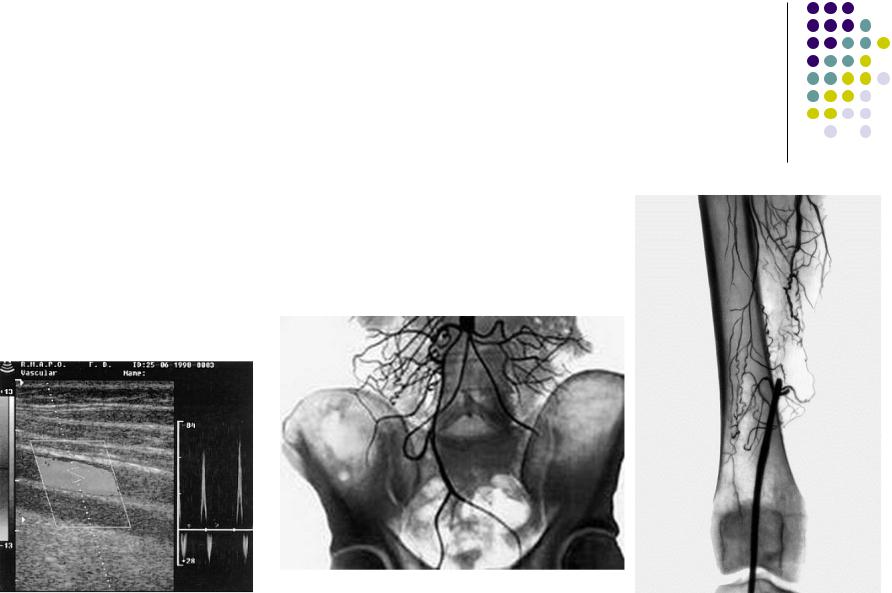

УЗАС. Эмболия ПБА

Контрастная ангиография.

Тромбоз брюшной аорты

Эмболия ПБА на фоне ОА